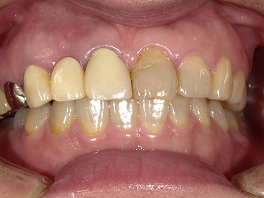

3人目の方も30台の女性の方です。右の一番前の歯が黒いことを気にして来院されました。

この方は、セラミックの歯を被せてほしいということで来院されましたが、グラディアダイレクトは歯を削る必要がないことを説明すると、歯を大切にしたいという思いで、グラディアダイレクトをすることになりました。

術前 ↓

術後

本人の希望で少し白めに仕上げています。この後にホワイトニングをすると回りの歯も白くなってさらに良くなるでしょう。